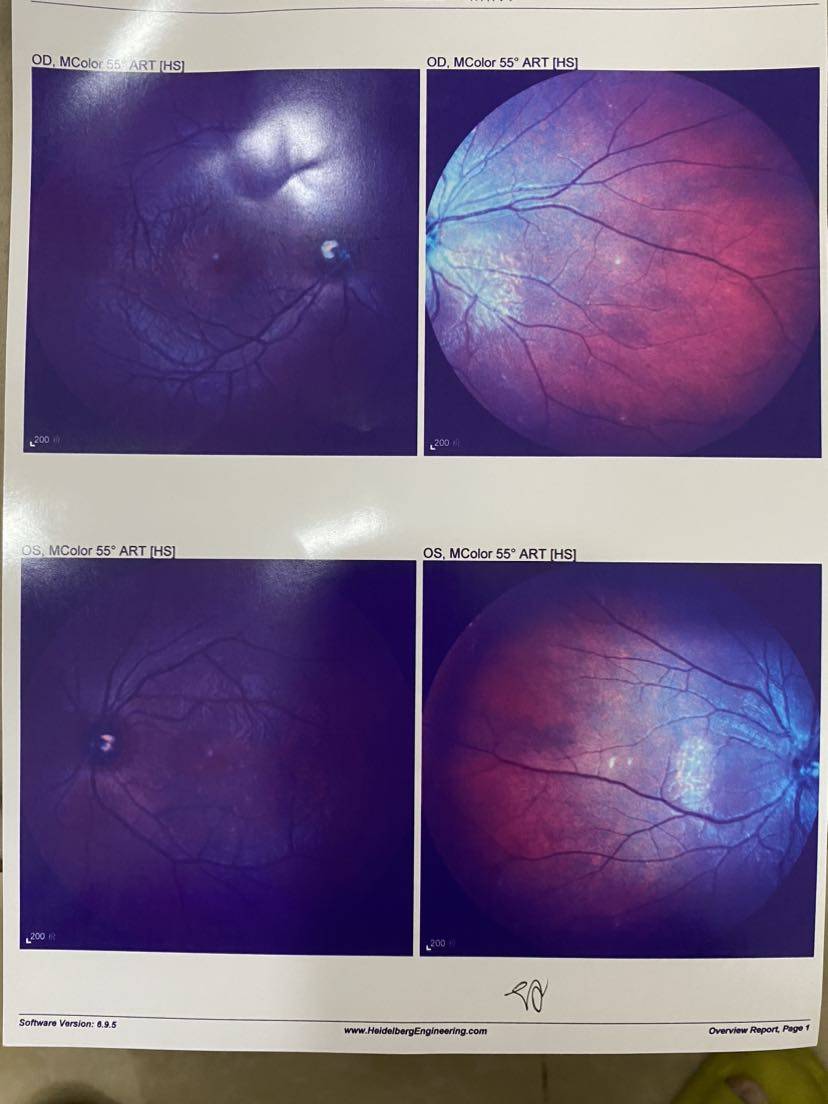

【小瞳验光】 【眼部彩色照】

【眼部彩色照】

翻开第一页就说,视网膜很明显有问题。 说是什么前膜,说目前还没影响到黄斑(?),不影响视力,但如果后期发展拉扯到黄斑看东西就会变形……然后听不懂😂

说是什么前膜,说目前还没影响到黄斑(?),不影响视力,但如果后期发展拉扯到黄斑看东西就会变形……然后听不懂😂

说是什么前膜,说目前还没影响到黄斑(?),不影响视力,但如果后期发展拉扯到黄斑看东西就会变形……然后听不懂😂

说是什么前膜,说目前还没影响到黄斑(?),不影响视力,但如果后期发展拉扯到黄斑看东西就会变形……然后听不懂😂一开始挺凝重的,然后我说我有狼疮,医生好像就淡定了?!?

最后把所有报告记录一下,医生说要保管好。千万不能折,那就拍照先留个底吧~

【眼部彩色照】

【眼部彩色照】